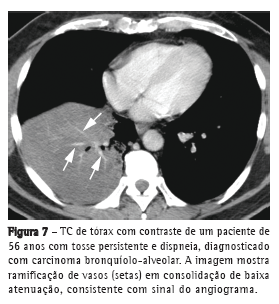

O sinal do angiograma pode ser visto na TC com contraste, consistindo em vasos pulmonares que se ramificam em meio à consolidação de baixa atenuação (Figura 7), usualmente correspondendo a espaços aéreos preenchidos por mucina. Primeiramente descrito como específico para a variante pneumônica do CBA, esse sinal pode ser visto em inúmeras entidades, como pneumonia infecciosa, edema pulmonar, pneumonia pós-obstrutiva, linfoma e metástases.(19)